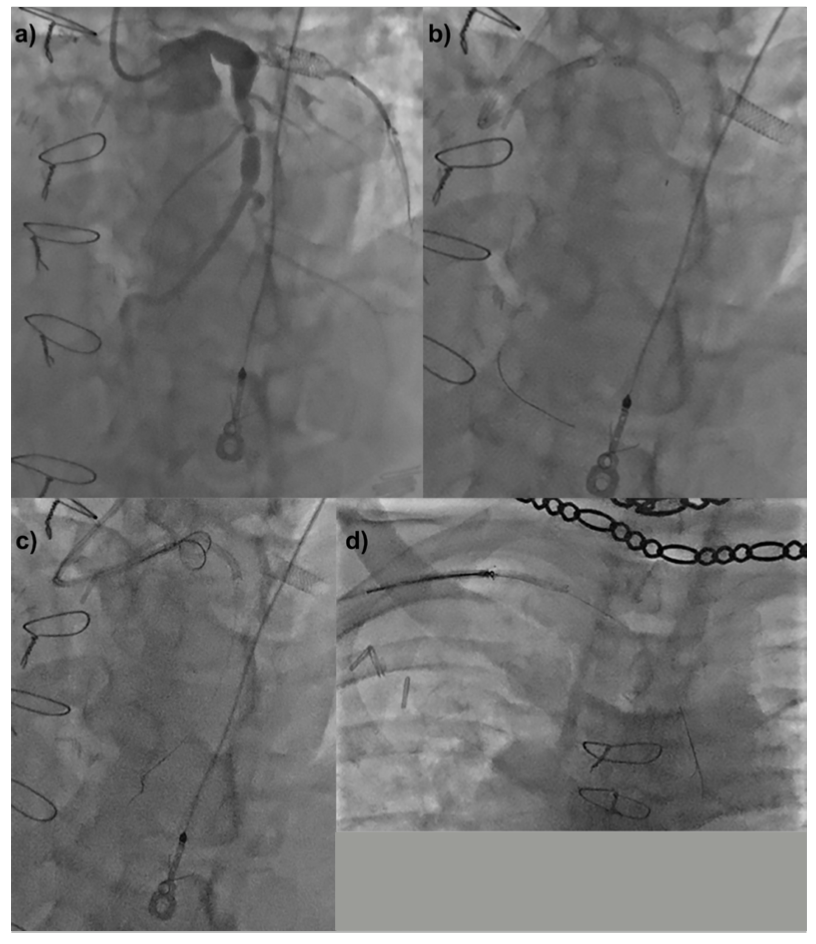

When dislodged stents remain on the coronary wire, the wire can be snared outside of the body (presnaring), and the snare loop advanced over the wire into the body to retrieve the stent (Figure 1). Presnaring may be a valuable technique to retrieve dislodged coronary stents when the stent remains on the coronary wire, as demonstrated in the following 2 patients.

A patient with unstable angina was found to have a severely diseased and tortuous proximal segment of an anomalous circumflex artery (Figure 2a). Stent delivery was unsuccessful due to proximal vessel angulation. The stent dislodged off the balloon during attempted withdrawal, but remained on the wire (Figure 2b). The balloon could not advance into the stent, and was therefore removed. A 9- x 15-mm En Snare (Merit Medical Systems) was loaded over the coronary wire outside of the body to presnare. The snare was brought out of the guide (Figure 2c), and with appropriate torqueing, the stent was snared and removed (Figure 2d). The procedure was completed using shorter overlapping stents for easier delivery, with buddy wire support (Video Series).